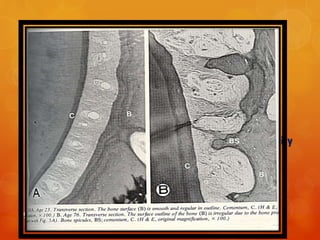

Severson et al (1978 )studied the age related changes in

The bone surface of the PDL was often irregular in outline

in contrast to that in young adults

Jagged in appearance with spicules of both lamellar and

non lamellar bone typically projecting into bundles of

suspensory fibers.

In histologic sections fibers interrupted by large

interstitial spaces appeared to lack either osseous or

cemental attachment

101